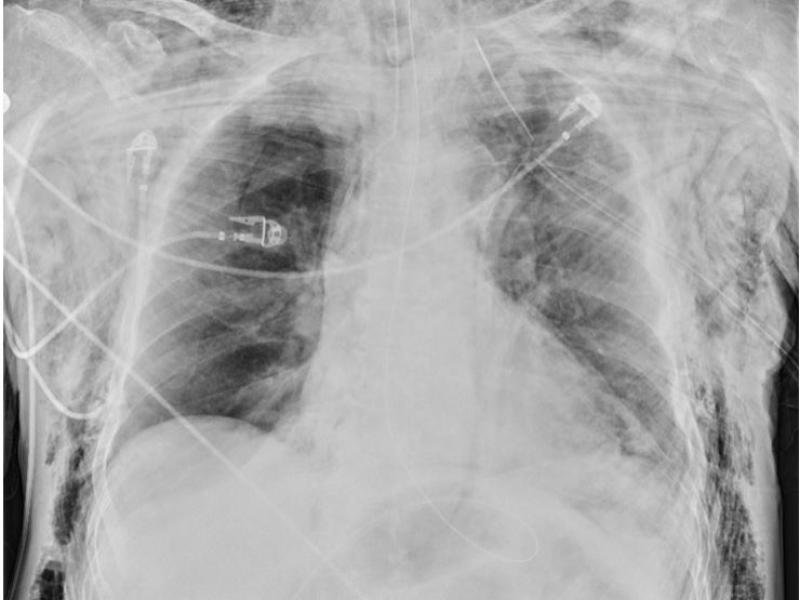

What's the Diagnosis? By Dr. Sarab Sodhi